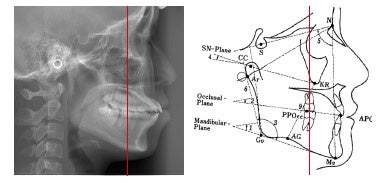

まず患者さんの骨格から診ていくというアプローチで臨みます。

それは背骨に乗っている頭の位置、頸椎の位置を正しい位置にし、そこに乗る頭蓋の位置を頸椎に対して正しくします。

左:奥歯の歯ぎしりや欠損のため顎関節が上にずれている右:歯並びをよくするには顎関節を正しい位置に戻すことが大事なポイント

つまり顎の関節の長さや形を整え、噛み合わせのバランスを良くすることから診ていきます。